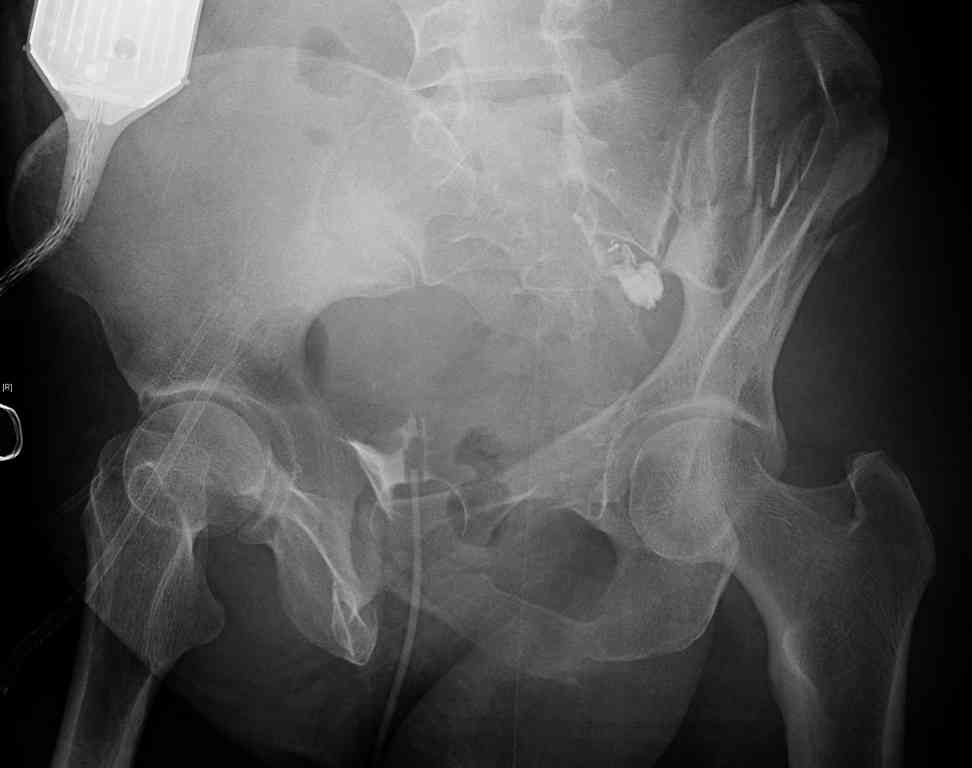

[Ortho] comminuted crescent fx

40 ish female ejected from car. Unstable, DPL negative, went to angio and had her pelvic bleeds embolized after many units of blood. GCS 6, floating elbow, clavicle, bothbones, etc.

My standard approach to  this pelvis would be posterior, reduce/lag/plate  thecrest, reduce/plate the caudal extent on the posterior crest and 1-2 lags back to front. In this case, the crest comminution seems to make plating all

the way to the ASIS useless, as the plate would be on free floating fragments. Would plating the posterior extent of the fracture to secure the

reduction at the SI joint and 2 screws back to front be sufficient fixation? Would anyone do a perc reduction and perc back to front screws, and would that be sufficient if the SI joint could be reduced (although I don't see how this could be accurately reduced closed). Would an ilioninguinal with a pelvic brim plate and posterior column screws be a better approach, although reducing the SI would be more indirect and less accurate?